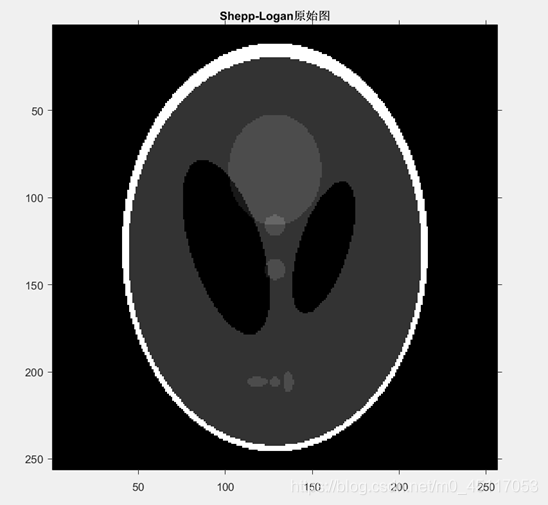

在MATLAB中使用phantom生成头部模型的图像,可用于测试radon和iradon或其他二维重建算法的数值准确性。P是由一个大椭圆(代表大脑)和几个较小的椭圆(代表大脑特征)组成的灰度图像作为原始仿体图像f(x, y)。调用公式如下:

其中字符型参数def指定要生成的头部模型的类型,在X射线断层扫描中采用 ‘Modified Shepp-Logan’’,因为Modified Shepp-Logan是Sheep-Logan 幻影的变体,其对比度得到了改进,有更好的视觉效果;并n指定模型图像中的行数和列数,取默认值为256。

P =phantom('Modified Shepp-Logan',256);%P为原图

%Modified Shepp-Logan是Sheep-Logan 幻影的变体,其对比度得到了改进,因此有更好的视觉效果

figure,imshow(P),title('Shepp-Logan原始图');